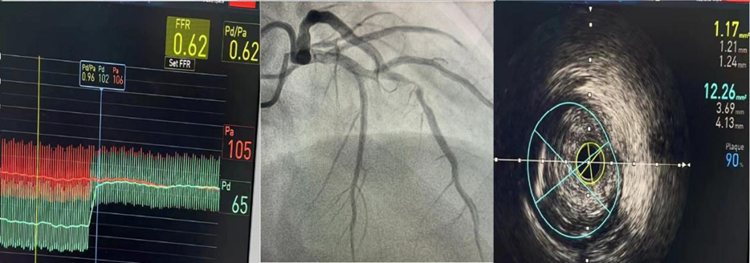

前降支中段严重狭窄,术前FFR 0.62,最小管腔面积1.17平方毫米